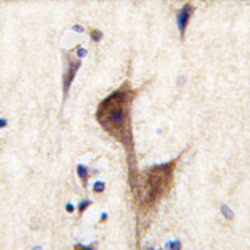

Immunohistochemistry

AP11651PU-N IHC

Full details